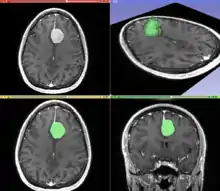

The figure "Visualization of Medical Imaging" illustrates several types of visualization: 1. the display of cross-sections as gray scale images; 2. reformatted views of gray scale images (the sagittal view in this example has a different orientation than the original direction of the image acquisition; and 3. A 3D volume rendering of the same data. The nodular lesion is clearly visible in the different presentations and has been annotated with a white line.